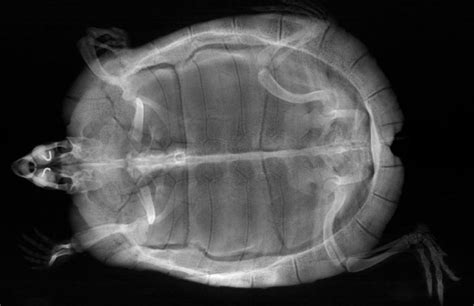

Alright, my fellow reptile aficionados, now for the really cool part: deciphering what your vet sees when they’re looking at that lateral turtle X-ray ! It’s like having a secret window into your turtle’s world, revealing all sorts of anatomical wonders and potential hidden issues. When your vet holds up that X-ray film (or points to the digital image on the screen), they’re not just seeing a jumble of shadows; they’re looking for specific structures and densities that tell a story about your turtle’s health. The lateral view provides a fantastic, uncluttered perspective that highlights the relationships between different organs and systems, making it incredibly powerful for diagnostic purposes. Let’s break down some of the key anatomical features they’re scrutinizing on a side view turtle X-ray .

Shell and Skeletal System

First up, let’s talk about the shell and the skeletal system . On a lateral turtle X-ray , the shell, comprising the carapace (top) and plastron (bottom), appears as a dense, bony outline. The vet will be looking closely at its integrity , checking for any signs of fractures, hairline cracks, or bone lesions that might not be visible externally. Sometimes, a trauma that seemed minor on the outside could have caused significant internal shell damage, and the side view X-ray is crucial for assessing this. They’ll also be evaluating the bone density of the shell and other skeletal structures, like the spine and limb bones. Reduced bone density, often appearing as thinner or less opaque bones on the X-ray, can be a tell-tale sign of Metabolic Bone Disease (MBD) , a common and serious condition in turtles caused by imbalances in calcium, phosphorus, and vitamin D3. MBD can manifest as generalized bone demineralization, pathological fractures, or abnormal bone growth. The lateral view allows for a clear assessment of the vertebral column, running along the length of the turtle’s body, checking for alignment, compression fractures, or any abnormal growths. The limb bones – humerus, radius, ulna, femur, tibia, fibula – are also visible, and the vet will be looking for fractures, dislocations, or other signs of injury or disease. Since turtles can be surprisingly resilient, they might not always show obvious signs of pain, making the X-ray an essential tool for uncovering these hidden skeletal problems. The clarity offered by the side view helps differentiate bone abnormalities from overlying soft tissues, ensuring an accurate diagnosis of skeletal health. The bony architecture of the shell, in particular, can reveal growth plate issues in younger turtles or degenerative changes in older ones, providing a comprehensive assessment of the animal’s osteological status.

Soft Tissue Structures and Organ Assessment

Now, moving deeper, the lateral turtle X-ray provides an incredible window into the soft tissue structures and internal organs . This is where the side view really shines, allowing for the assessment of organs that would be heavily superimposed in a top-down image. One of the most important areas is the lungs . In a lateral X-ray , the lungs appear as relatively clear, air-filled spaces located dorsally (towards the back) within the shell. The vet will be meticulously examining these lung fields for any abnormal densities, fluid accumulation (which would show up as hazy or opaque areas), or granulomas (small, dense masses). These findings are classic indicators of respiratory infections like pneumonia, which are common in turtles, especially those kept in improper environmental conditions. The side view helps distinguish lung pathology from other dense structures, such as the shell or overlying limbs, giving a much clearer picture of the severity and distribution of the infection. A healthy lung should appear clear and well-inflated, and any deviation from this normal appearance is a cause for concern.